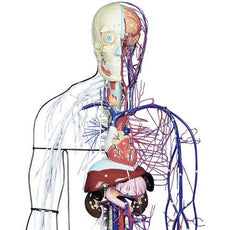

Physical Structure(LP)/GEORGE OHTSUKA/ジョージ大塚/ジョージ, Full-Figure Nervous and Circulatory System – GTSimulators.com,

Full-Figure Nervous and Circulatory System – GTSimulators.com, Full-Figure Circulatory System with Half Skeleton

Full-Figure Circulatory System with Half Skeletonジャズレコード MJQ 2LPセット